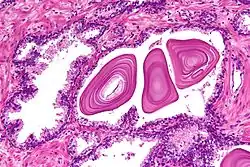

Microanatomia

A próstata consiste em tecido glandular e conjuntivo. Células altas em forma de coluna formam o revestimento (o epitélio) das glândulas.[1] Estas formam uma camada ou podem ser pseudoestratificadas.[3] O epitélio é altamente variável e áreas de células cuboidais baixas ou planas também podem estar presentes, com epitélio transicional nas regiões externas dos ductos mais longos.[9] As glândulas são formadas como muitos folículos, que drenam para os canais e, subsequentemente, para 12–20 ductos principais. Estes, por sua vez, drenam para a uretra à medida que passa pela próstata.[3] Há também uma pequena quantidade de células planas, que ficam próximas às membranas basais das glândulas e agem como células-tronco.[1]

O tecido conjuntivo da próstata é composto de tecido fibroso e músculo liso. O tecido fibroso separa a glândula em lóbulos.[1] Ele também fica entre as glândulas e é composto por feixes de músculos lisos orientados aleatoriamente que são contínuos com a bexiga.[10] Com o tempo, secreções espessadas chamadas corpora amylacea se acumulam na glândula.[1]

Glândulas microscópicas da próstata

Glândulas microscópicas da próstata